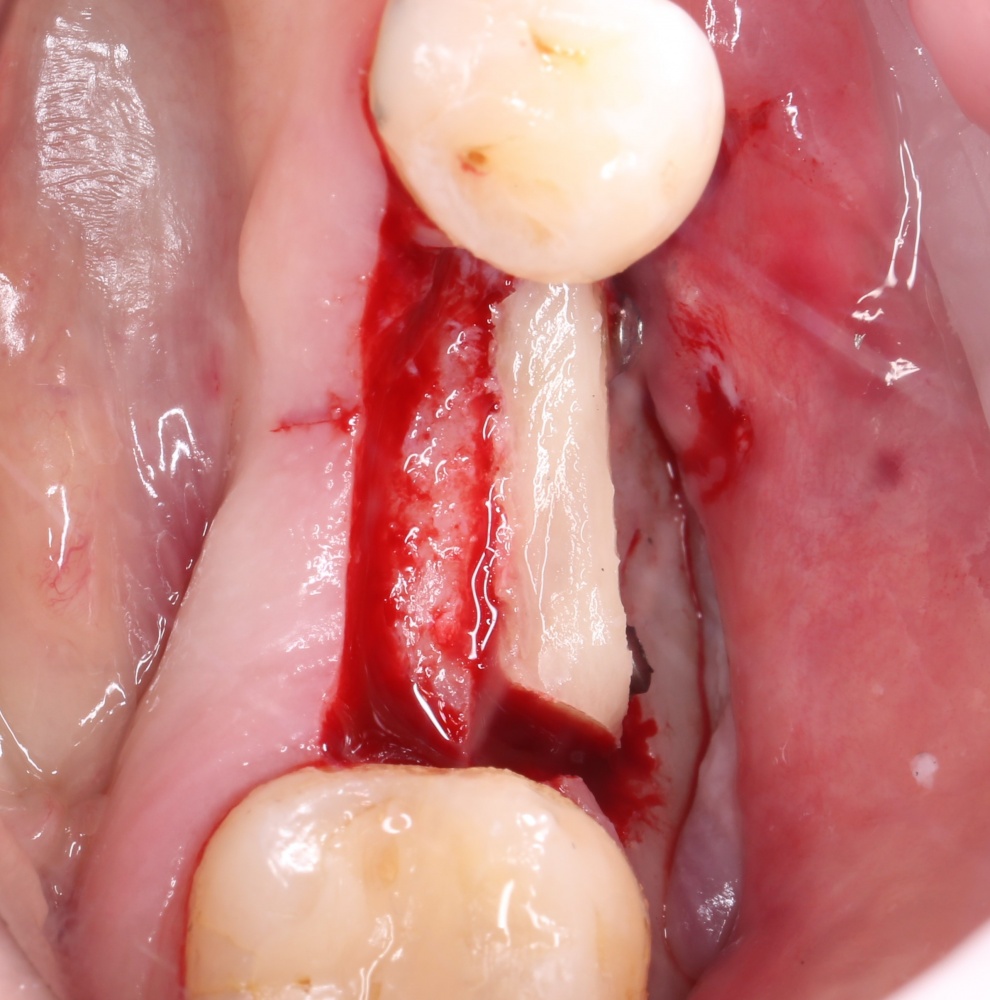

Для получения костного блока, мы открываем донорскую зону, наружную косую линию нижней челюсти.

Получение костного аутотрансплантата.

Здесь потребуется пародонтологический зонд с миллиметровой разметкой или какой-то другой измерительный прибор (операционная линейка). Ранее по КЛКТ я измерил костный дефект, теперь нужно нанести границы будущего костного блока на донорскую зону.

Ремарка: некоторые доктора предлагают делать хирургические шаблоны или выкройки специально для точного забора костного блока. На мой взгляд, это чрезмерное усложнение - во-первых, использование подобных шаблонов или выкроек требует увеличения площади раны, во-вторых, это увеличивает время и стоимость лечения, в-третьих, на этом этапе не требуется высокая точность, поскольку блок всё равно потребует адаптации.

Иными словами, важна не точность, а быстрый, аккуратный и, что главное, малотравматичный забор аутотрансплантата.

Для получения костного блока мы использовали ультразвуковую пьезохирургическую систему. Это самый удобный и безопасный инструмент для проведения подобных манипуляций. С помощью него мы сформировали и выделили костный блок. Он должен отделяться легким движением остеотома или элеватора. Как это сделать правильно — читай здесь>>